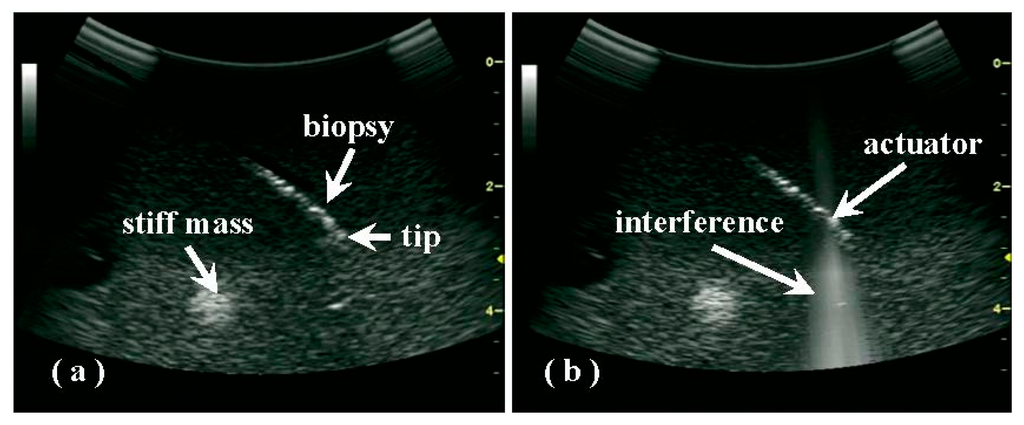

Although the acoustic pressure produced by the actuator was quite weak, the interference that occurred with the diagnostic pulses could also be detected by the convex array and diagnostic circuit. When the actuator was turned on, bright and clear lines in a conical shape appeared in the sonography; the location of the actuator could be easily determined from these lines (see Figure 4). After changing the ultrasonic emission from continuous to pulsed mode, the interference appeared to be flashing (data not shown).

Because of speckle noise in the sonography, the biopsy needle did not appear as continuous hyper-echoic pixels, but rather appeared as discrete ones (Figure 4). Therefore, the needle tip, which may be below the sonographic resolution, was not determined easily and reliably using conventional B-mode imaging, especially inside a target with many hyperechoic scatters and significant heterogeneities. Due to its small size, the actuator itself does not show up in the sonography and introduce any shadowing effect. It is found that with increasing sample heterogeneity and structural complexity, the variation in the distance between the PZT actuator and the assumed needle tip, as measured using the built-in caliper in the sonography increased from 2.9 ± 0.6 mm in the gel phantom to 2.6 ± 1.4 mm in ex vivo tissue (as listed in Table 1). Thus, extending from the site of interference by the predetermined distance (i.e., the actual value between the actuator and the needle tip) along the biopsy orientation may be an easy method of estimating the position of the biopsy tip, which may not always be visible in the sonography.